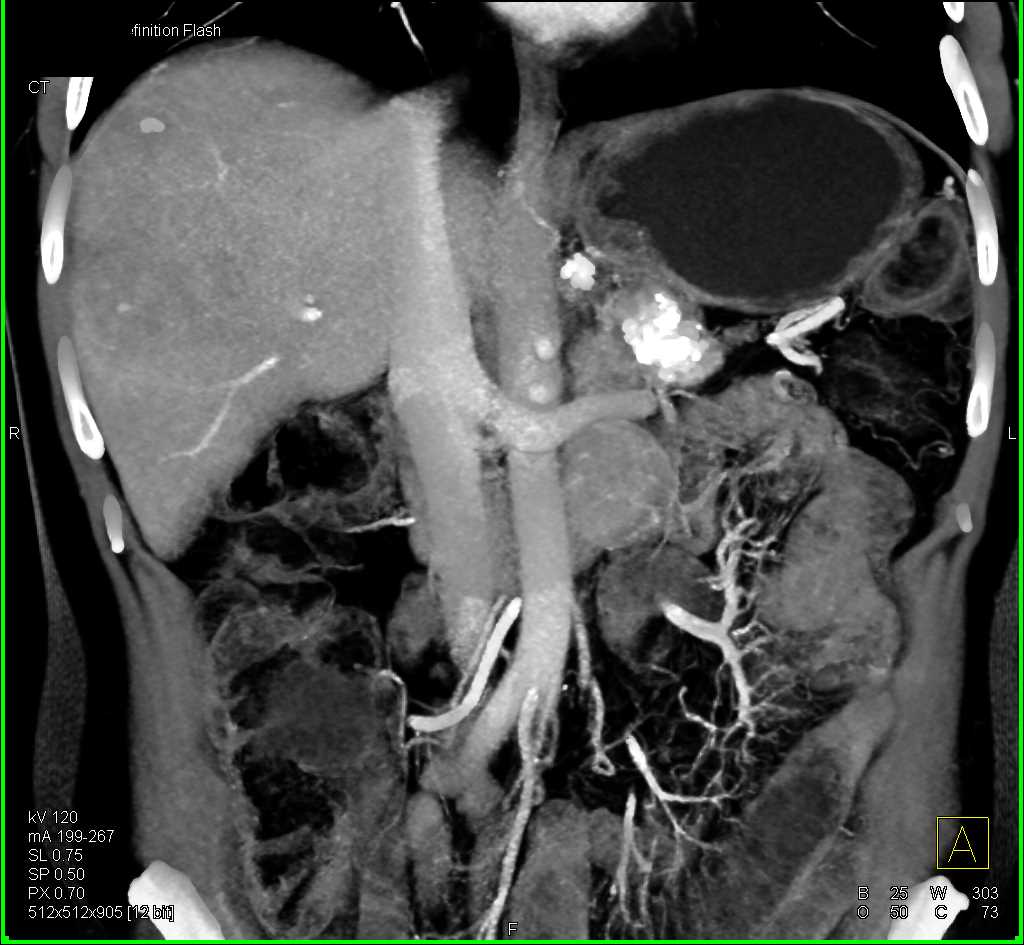

Neuroendocrine Tumor Pancreas